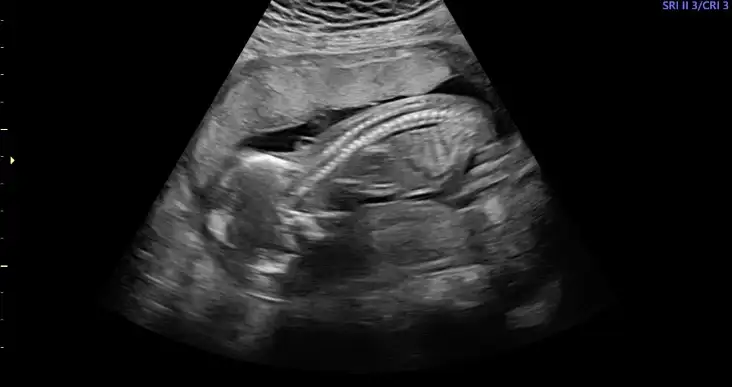

valla benim doktor cok fazla usg de bakio tek tek anlatiyor her seferinde bu sefer sende sorGüya 4.bebişm diğerlerinde gösterilerdi tek tek. Usg fotosunu bile anlamıyorum bu konuya uzağım. Tekrar gittiğimde videoya alacağım

Önceki usgde 15 sanırım orda pipi değil pitis vardıBenim 16da böleydi benek secdede asla kıpırdamadı uğraşmadıda doktor alttan baktı ama 1 kere baktı kız dedine foto ne bişi düzgün vermedi bunu vermiş muayene 10dk bulmamıştır yani o sebeple 20bekliyorum yinede

Evet onda şunu verdi, buna bakış bende kız diyorumÖnceki usgde 15 sanırım orda pipi değil pitis vardı